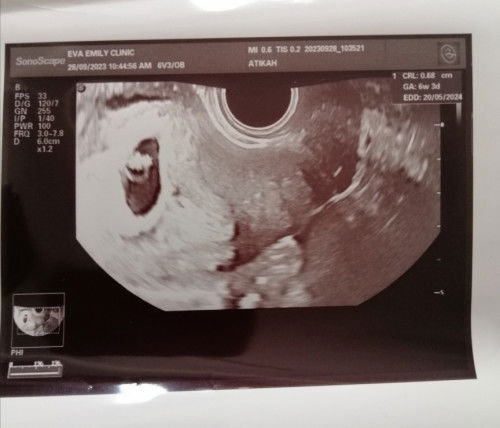

Scan yg pertama kedua nampak jg mcm yolk sac.. Scan terakhir jadi kosong. Knpa eh? Doktr ckp yg awal tu rasanya bayangan je.. Pelik betul.. Dua gmbr tu hasil dari tvs.. Sapa ad pnglmn yg sama.. Bleh share. Mcm mna tips utk rawatan slps tu. Spya kes mcmni tak berulang smula.. #bantusharing #pleasehelp #ingintahu #seriusnanya